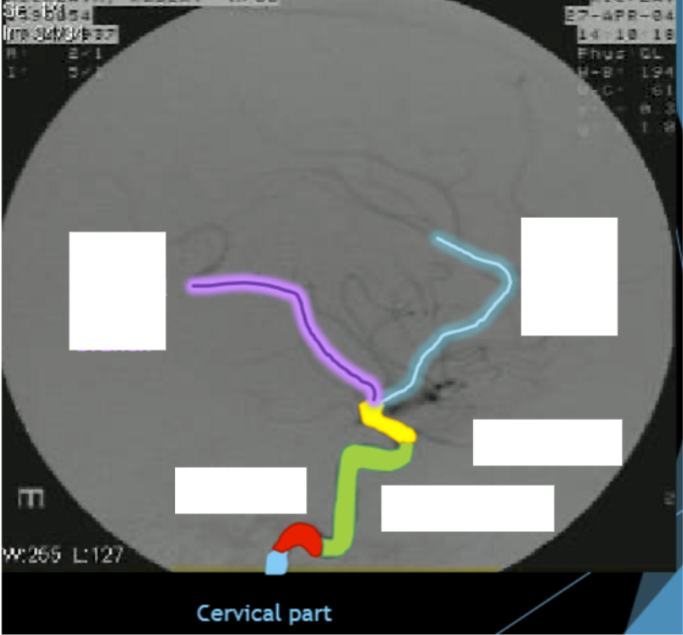

Please label the internal carotid artery (ICA)